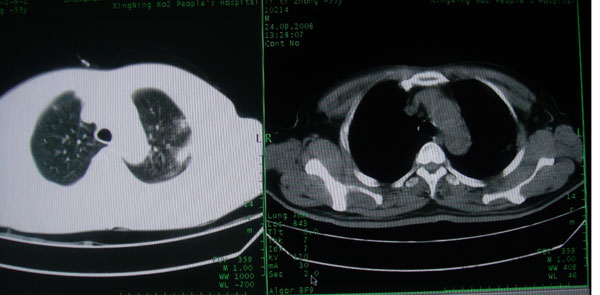

患者男性58岁因二周前起咳嗽,今天胸片示左上肺占位性病变行ct检查,无发热,无咯血痰.

左上肺感染性病变,结核伴空洞形成可能,左上肺膨胀不全

左肺上叶病灶,实变但见含气支气管、空洞但未见壁内结节及积液;

考虑:①感染性病变(包括特殊感染型肺tb)

②肿瘤性病变(考虑患者年龄比较大的关系/所以不排除)

初学者。。。左肺空洞性病变,并可见阻塞性肺不张改变,鉴于患者为老年男性,且临床症状仅有咳嗽,全身中毒症状不明显,所以我首先考虑为左肺癌性空洞并左侧肺门淋巴结转移伴左肺阻塞性肺不张。结核性空洞放于第二位考虑,可以进行相关实验室检查。希望能有病理结果,谢谢!!!!!

左肺上叶实变影,内见支气管充气征及空洞影,病人年龄较大,无发热及结核中毒症状,心影左移,未见纵隔淋巴结肿大;不知实验室检查结果如何?有否嗜酸细胞增多,有没有进行治疗?就目前资料首先考虑1.感染性病变,2.慢性嗜酸性肺炎?可结合实验室检查并短期治疗复查,肺癌不能排除。